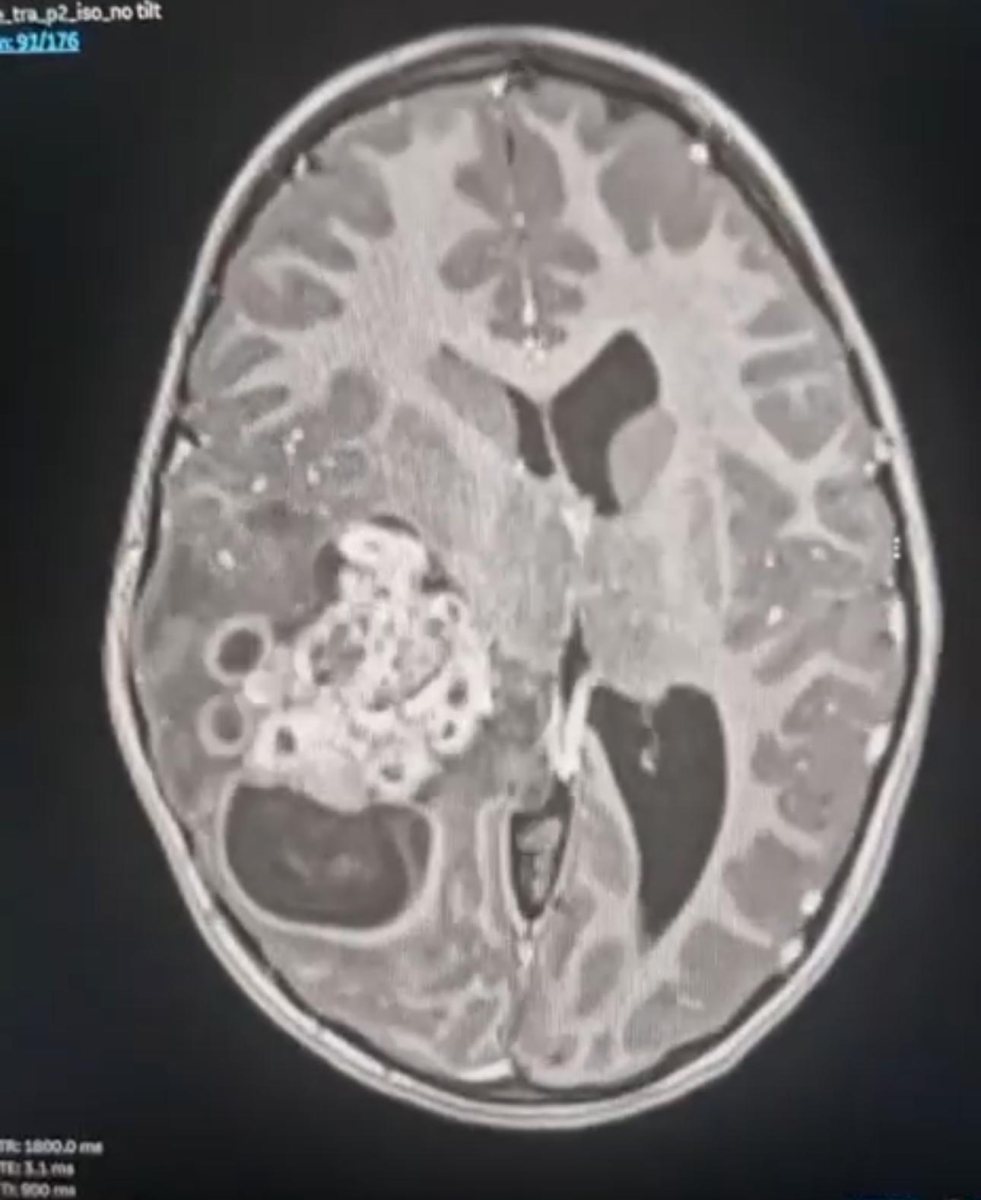

אריאלה אושפזה במחלקה לטיפול נמרץ ילדים לצורך בדיקת CT, שהעלתה כי היא סובלת מגידול בהיקף משמעותי בצידו הימני של המוח, שדורש ניתוח ניורוכירורוגי דחוף. מדובר בגידול שגורם ללחץ על המוח ומוביל לחולשת צד, לישנוניות, להקאות, לכאבי ראש ועוד. צוות רחב שכלל מומחי אונקולוגיה ילדים, בהובלת ד"ר איריס פריד וצוות טיפול נמרץ ילדים בהובלת ד"ר זאק בראון והאחות טלי וייס, ליוו את הטיפול באריאלה.